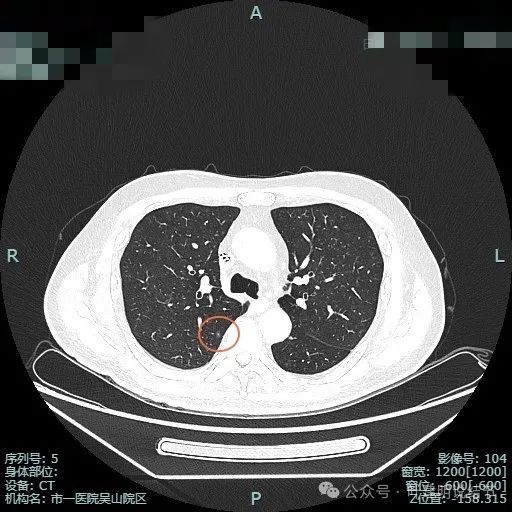

先看薄层平扫不同结节的情况:

左下叶背段主病灶,密度高,是实性的,表面不平,有点像土豆。

左下背段病灶实性,密度较高,紫色箭头处表面有细锯齿状,桔色箭头示有血管发出分支进入病灶且进入的血管到了结节边上有增粗。

多支血管进入,病灶有膨胀感。

边缘毛糙,细毛刺或锯齿状明显。

整体膨胀性较明显,有少许磨玻璃成分,周围肺野较清晰,血管与之关系密切。

细小毛刺可见,少许磨玻璃成分,整体轮廓较清。

邻近血管与之近但两者间有间隙,说明非普通伴水肿的炎性病灶;病灶膨胀感显得较明显,有鼓鼓的感觉。

进入的血管壁显得毛糙,有异常增粗,结节与邻近血管之间有间隙征,整体有膨胀感。

像个腰子的形态,靠下侧深凹进去,说明有收缩力吗?还是月牙铲征?

病灶表面细锯齿状,整体膨胀性明显,血管进入并异常增粗,整体轮廓清,周围肺野清晰。

病灶表面不平,形态略不规则,血管进入,边缘细锯齿状。